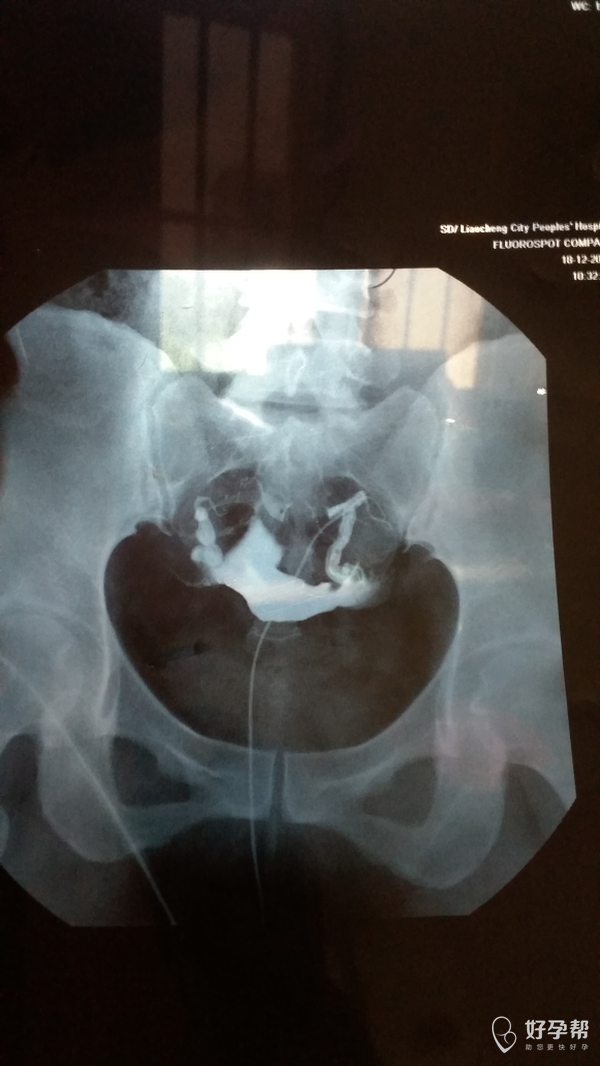

您好,双侧输卵管通畅的,但是双侧输卵管远端增粗,盆腔弥散不好,不排除盆腔粘连。